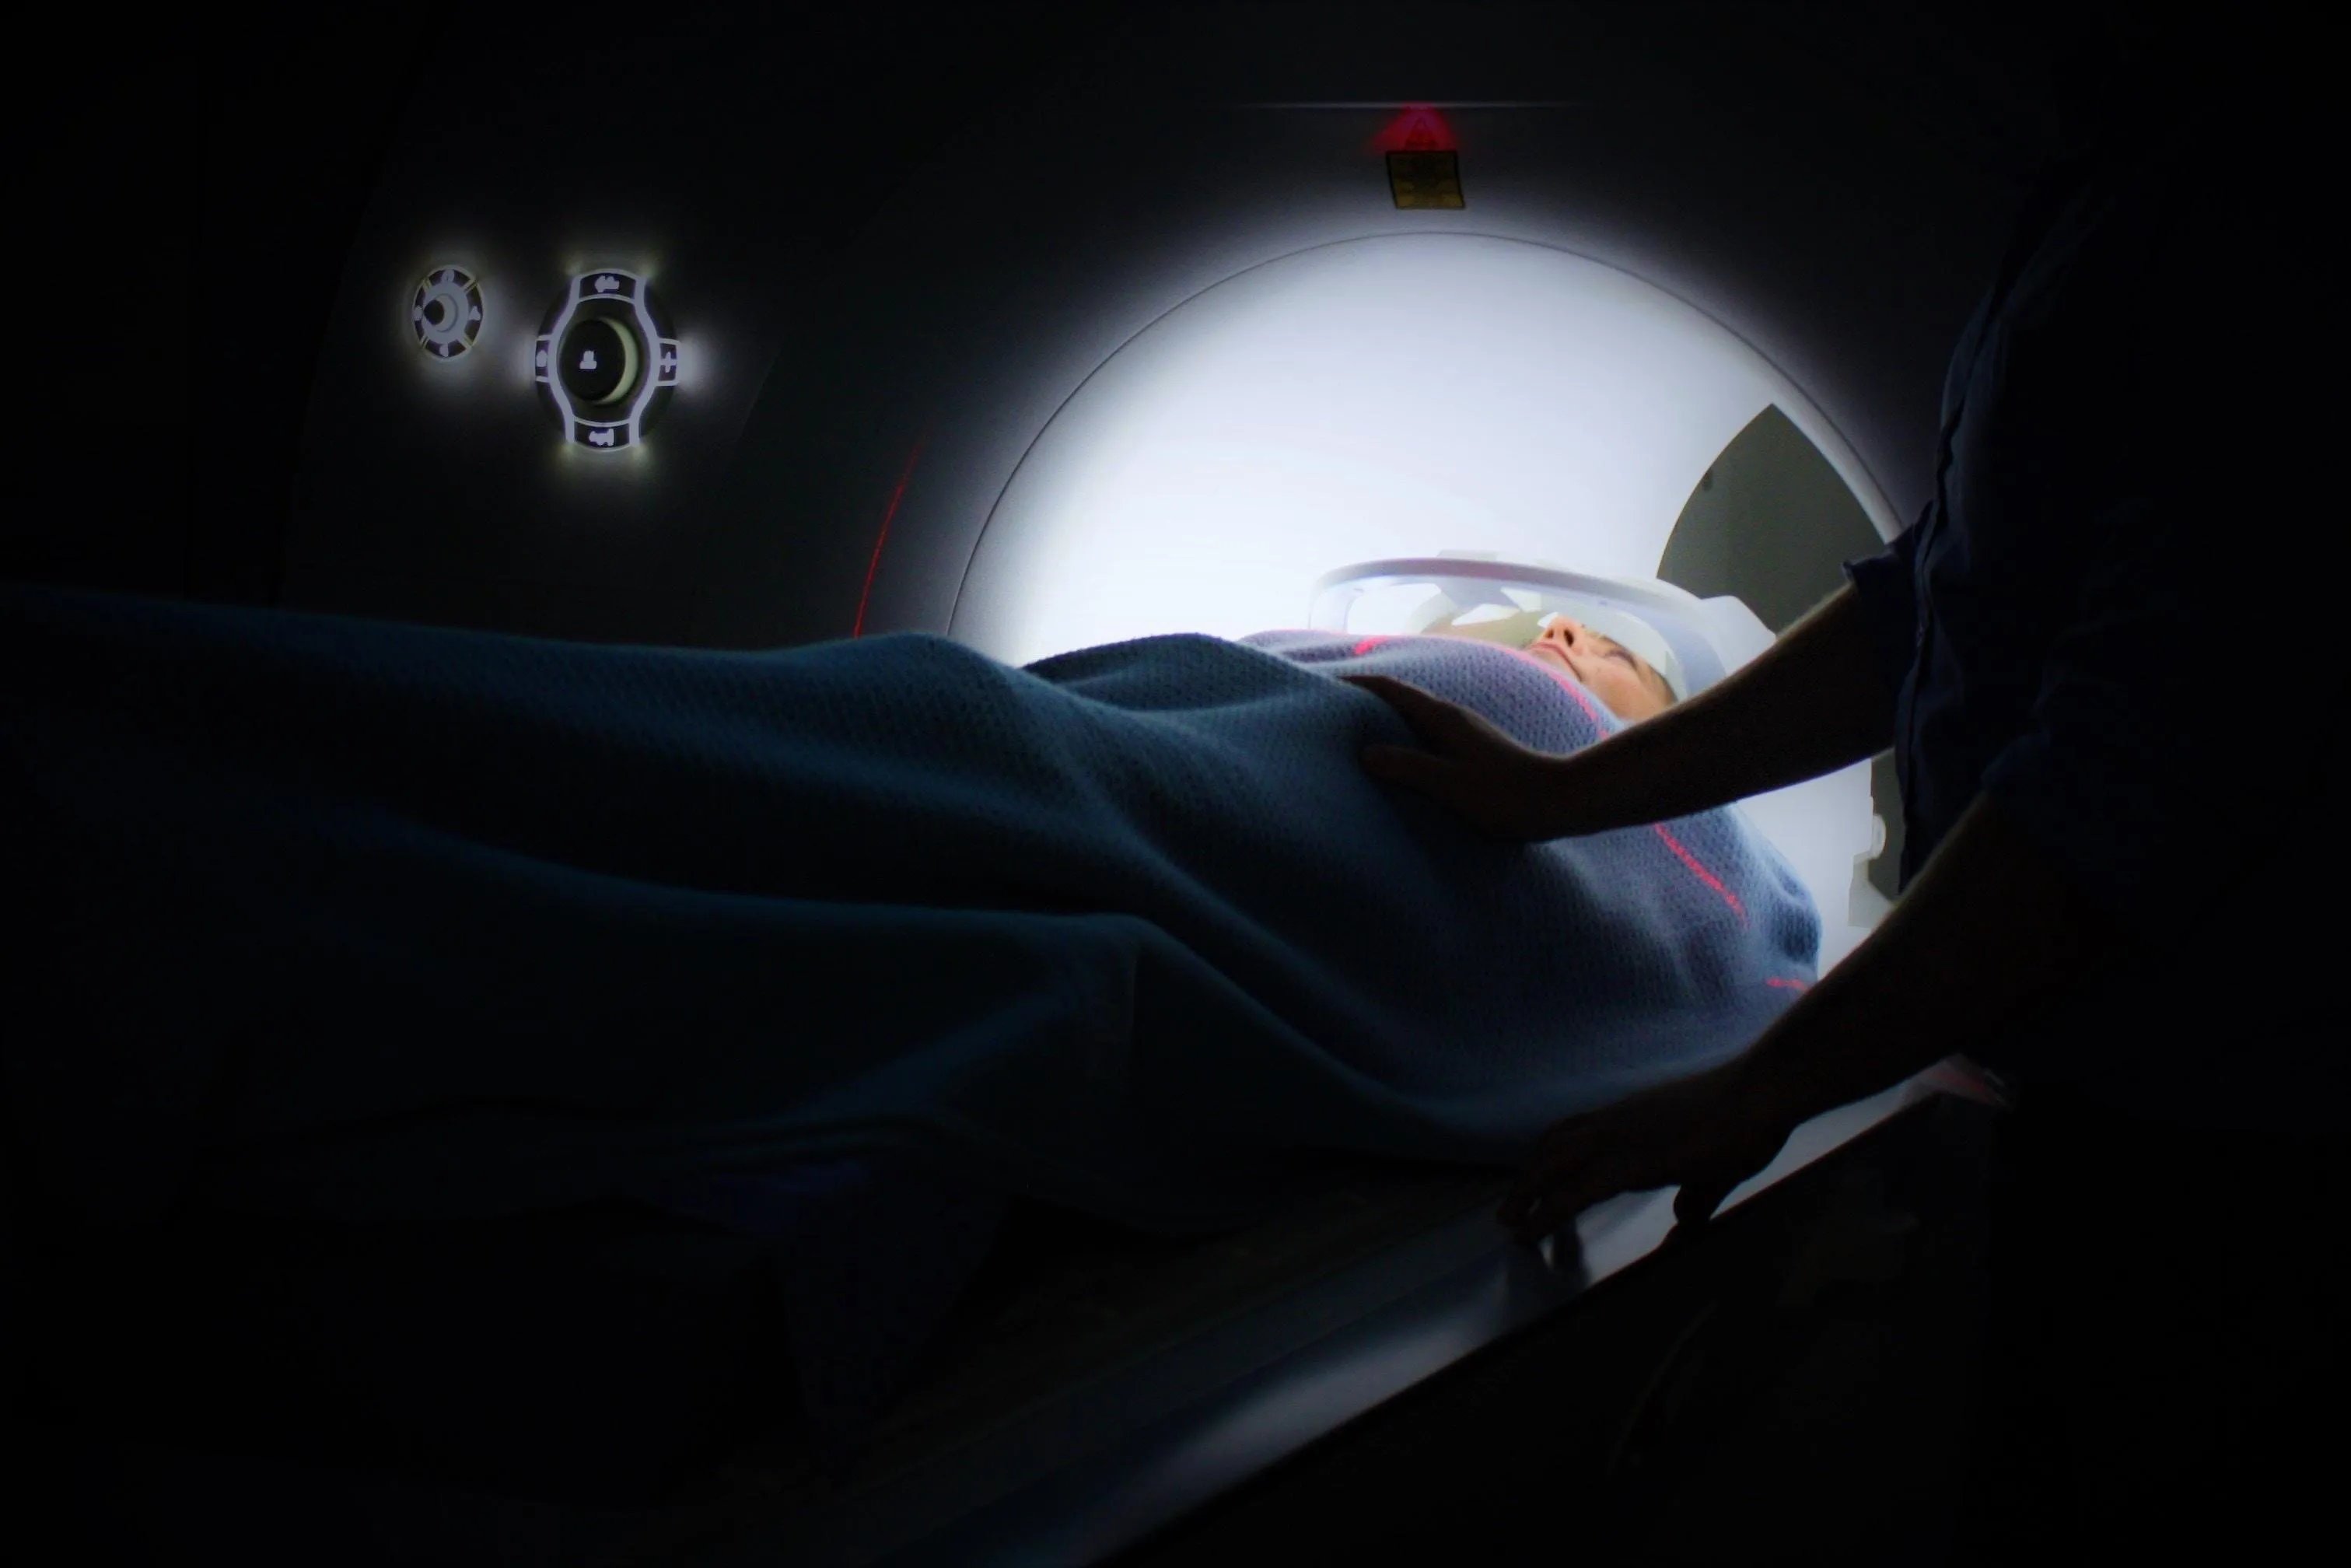

Вчені довели свою теорію, провівши дослідження за участы 54 добровольців від 55 до 80 років з одним із чинників, який збільшував вірогідність розвитку інсульту: апное, куріння, високий рівень холестерину і тиск. Захворювання судин діагностувалося за допомогою сканування судин мозку і білої речовини на апараті МРТ.